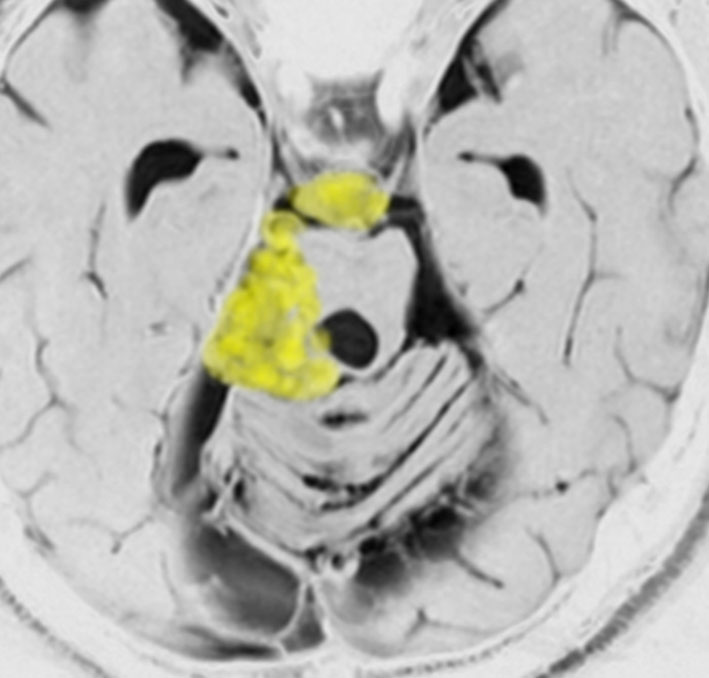

30歳くらいの時に初回の開頭手術で部分摘出を受けて,現在70代の患者さんの画像です。黄色は今も残っている腫瘍です。2度目の開頭手術,3度目の開頭手術では癒着で脳幹部や脳神経からの剥離が全くできませんでした。現在でも脳幹部に入り込むように腫瘍がゆっくり大きくなっていて,体幹失調のために車椅子生活です。顔面神経麻痺,嚥下障害,構語障害,眼球運動障害などもあります。髄液吸収障害による水頭症を併発してシャント手術も受けています。

この患者さんの40年の経過はいろいろなことを教えてくれます。似たような患者さんをたくさん見てくると,初回手術で取りきれなかった類表皮のう胞を,2度目の開頭手術で完全摘出することはとても難しいという経験を積みます。

数十年後のことを考えるのであれば,初回手術で完全摘出するべきです